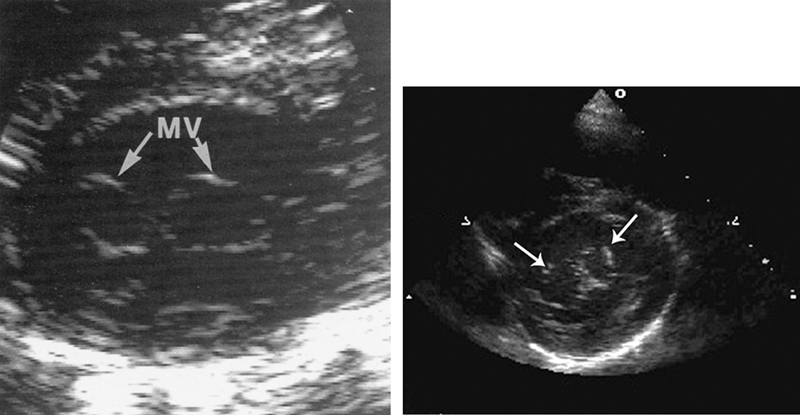

فحوصات تشخيصية لبعض امراض القلب والشرايين التاجية